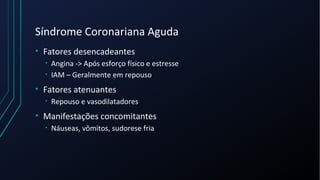

Dor torácica pode ter diversas causas, incluindo cardíacas como síndrome coronariana aguda, dissecção de aorta e pericardite, e não cardíacas como problemas pulmonares, musculoesqueléticos e do trato gastrointestinal. É importante avaliar a história clínica, características da dor e exame físico para identificar a possível causa e orientar o tratamento adequado.